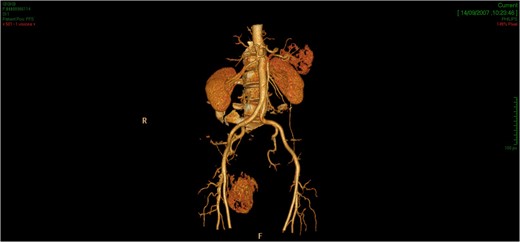

The tridimensional reconstruction shows the rich vascularization of the neoplasm.